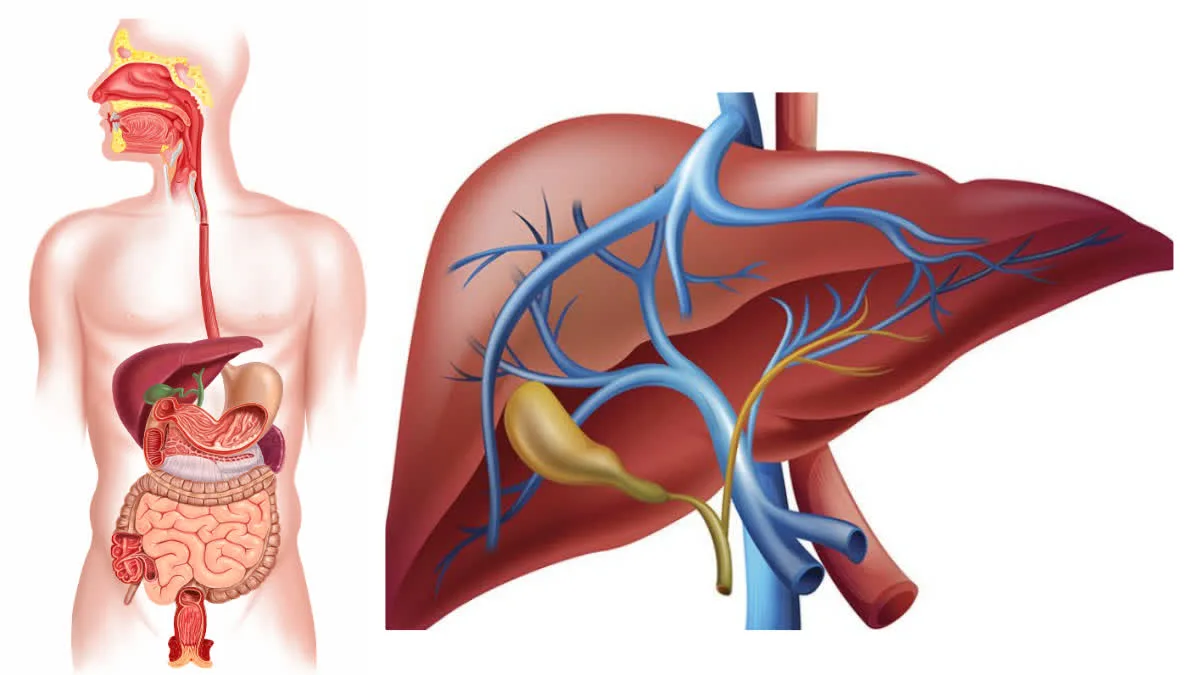

लिवर हमारे शरीर का एक जरूरी अंग है. यह शरीर से टॉक्सिन और नुकसानदायक चीजों को फिल्टर करके निकालता है. यह बाइल भी बनाता है, जो पाचन में मदद करता है, और लाल रक्त कोशिकाओं के प्रोडक्शन में भी भूमिका निभाता है. इसलिए, अच्छी सेहत के लिए अपने लिवर का ख्याल रखना बहुत जरूरी है.

गामा-ग्लूटामिल ट्रांसफरेज (GGT) एक एंजाइम है जो मुख्य रूप से लिवर, बाइल डक्ट और किडनी में पाया जाता है, और यह लिवर की बीमारी, नुकसान या बाइल डक्ट की समस्याओं के लिए एक सेंसिटिव मार्कर का काम करता है. यह अमीनो एसिड ट्रांसपोर्ट और ग्लूटाथियोन मेटाबॉलिज्म में भूमिका निभाता है.

GGT अमीनो एसिड और पेप्टाइड्स को कोशिकाओं में पहुंचाने में मदद करता है और लिवर के डिटॉक्सिफिकेशन प्रोसेस को सपोर्ट करता है. यह ग्लूटाथियोन, जो एक पावरफुल एंटीऑक्सीडेंट है, उसे तोड़ने में भी मदद करता है. इस तरह, GGT लिवर के हेल्दी फंक्शन और ओवरऑल सेलुलर हेल्थ को बनाए रखने में अहम भूमिका निभाता है.